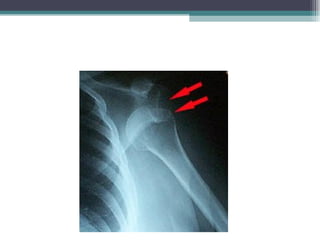

Fraturas Quanto à exposição do foco de fratura  Fechada: o foco de fratura está protegido por partes moles e com pele íntegra.  Aberta ou exposta: o foco de fratura está em contato com o meio externo, com o osso exteriorizado ou não. A pele, nestes casos, está sempre lesada. O grau de lesão dessas partes moles permite classificar as fraturas expostas. A lesão da pele pode ocorrer pelos fragmentos ósseos e pelo manuseio intempestivo da vítima, tornando uma fratura fechada em aberta.

Fraturas Quanto àexposição do foco de fratura Fechada: o foco de fratura está protegido por partes moles e com pele íntegra. Aberta ou exposta: o foco de fratura está em contato com o meio externo, com o osso exteriorizado ou não. A pele, nestes casos, está sempre lesada. O grau de lesão dessas partes moles permite classificar as fraturas expostas. A lesão da pele pode ocorrer pelos fragmentos ósseos e pelo manuseio intempestivo da vítima, tornando uma fratura fechada em aberta.